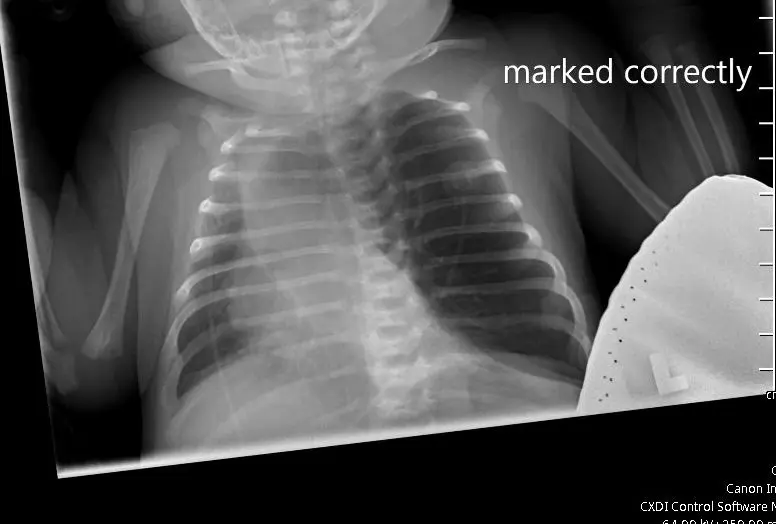

Initial vitals in the ED showed hypoxemia, tachypnea, and fluctuating oxygen saturations were between 65-100% on room air. A chest X-ray is shown (Figure 1).

Due to an x-ray obtained while the patient was on the pediatrics floor, there were concerns for an underlying tension pneumothorax. The patient was transported to the PICU, where upon admission an urgent needle decompression was performed. However, upon performing the same, there was no change in the patient's vitals, nor was there a gush of air emitted from the needle that was placed. To further delineate the cause of the findings seen on the x-ray, a CT chest with IV contrast was performed (Figure 2). This image study confirmed the diagnosis of left upper lobe congenital emphysema. Her condition was managed with surgical resection of the left upper lobe emphysematous lobe. Her respiratory status improved after surgical resection with her breathing without any distress.

The diagnosis of CLE can be challenging as it may mimic other conditions such as tension pneumothorax or pulmonary interstitial emphysema.2 Chest X-rays and CT scans are the imaging modalities of choice to confirm the diagnosis. In this patient, the initial X-ray raised suspicion for CLE, which was later confirmed by a CT scan showing hyperinflation of the left upper lobe and atelectasis of the left lower lobe.